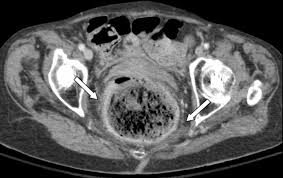

Steric colitis can be fatal and requires immediate treatment. The importance of early recognition is very high to avoid complications associated with late diagnosis. Early diagnosis by computed tomography (CT) demonstrates fecaloma, focal thickening of the dilated sigmoid and rectal wall representing edema due to ischemia or ulceration, and peri-suture or perirectal fat. Most often, the lesion occurs in the sigmoid and rectosigmoid colon, which, in addition to the relatively poor blood supply, have the narrowest diameter of the colon, which provides a higher intraluminal pressure.

Therefore, early diagnosis and treatment with bowel cleansing and stool disinfection are necessary to avoid the fatal consequences of this condition. This early assessment is performed with CT findings with focal thickening of the colon wall, curling of pericolic fat in the segment showing fecal blockage, and the presence of extraluminal gas bubbles or abscess.